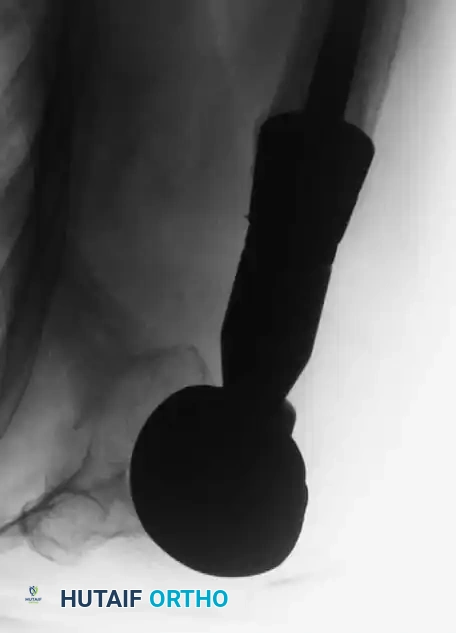

Fig. 22-19: (A) Anteroposterior view of the left hip of a 50-year-old woman with a history of breast cancer, disease-free for 2 years. A lytic lesion is seen in the femoral neck. Although the most likely diagnosis is metastatic carcinoma, a biopsy must be performed. This lesion proved to be a malignant fibrous histiocytoma (primary sarcoma). (B) Anteroposterior view after wide resection and endoprosthetic reconstruction. Prophylactic fixation of this presumed metastasis would have severely compromised her oncologic outcome.